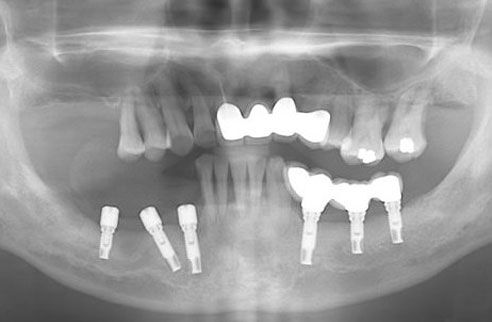

图为我院收治的种植牙典型失败案例口腔全景图

在春天牙科,华西的谭教授看过李大爷的牙片,诊断道:“李大爷的种植手术是很失败的,种植体歪七扭八,受力不均造成种植体断裂,而且还出现了严重的牙骨吸收”,现在只能给他先缓解牙痛问题,而种植体这种根本问题暂时得不到很好的解决。

实际上,李大爷种植牙失败的根本原因有两点:第一,因为医生技术不过关也不负责任,导致种植时没有将种植体准确的安放于牙骨上;第二,因为贪图便宜,选择了没有质量保障的种植体,造成牙骨无法生长并包裹住种植体,而最终导致种植失败。更悲惨的是,所造成的后遗症很难解决,也无法第二次进行种植。